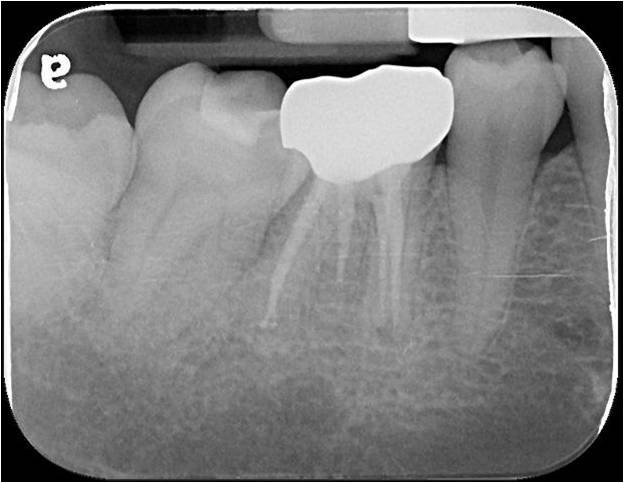

治療前,根管治療後組織良好

全鋯冠